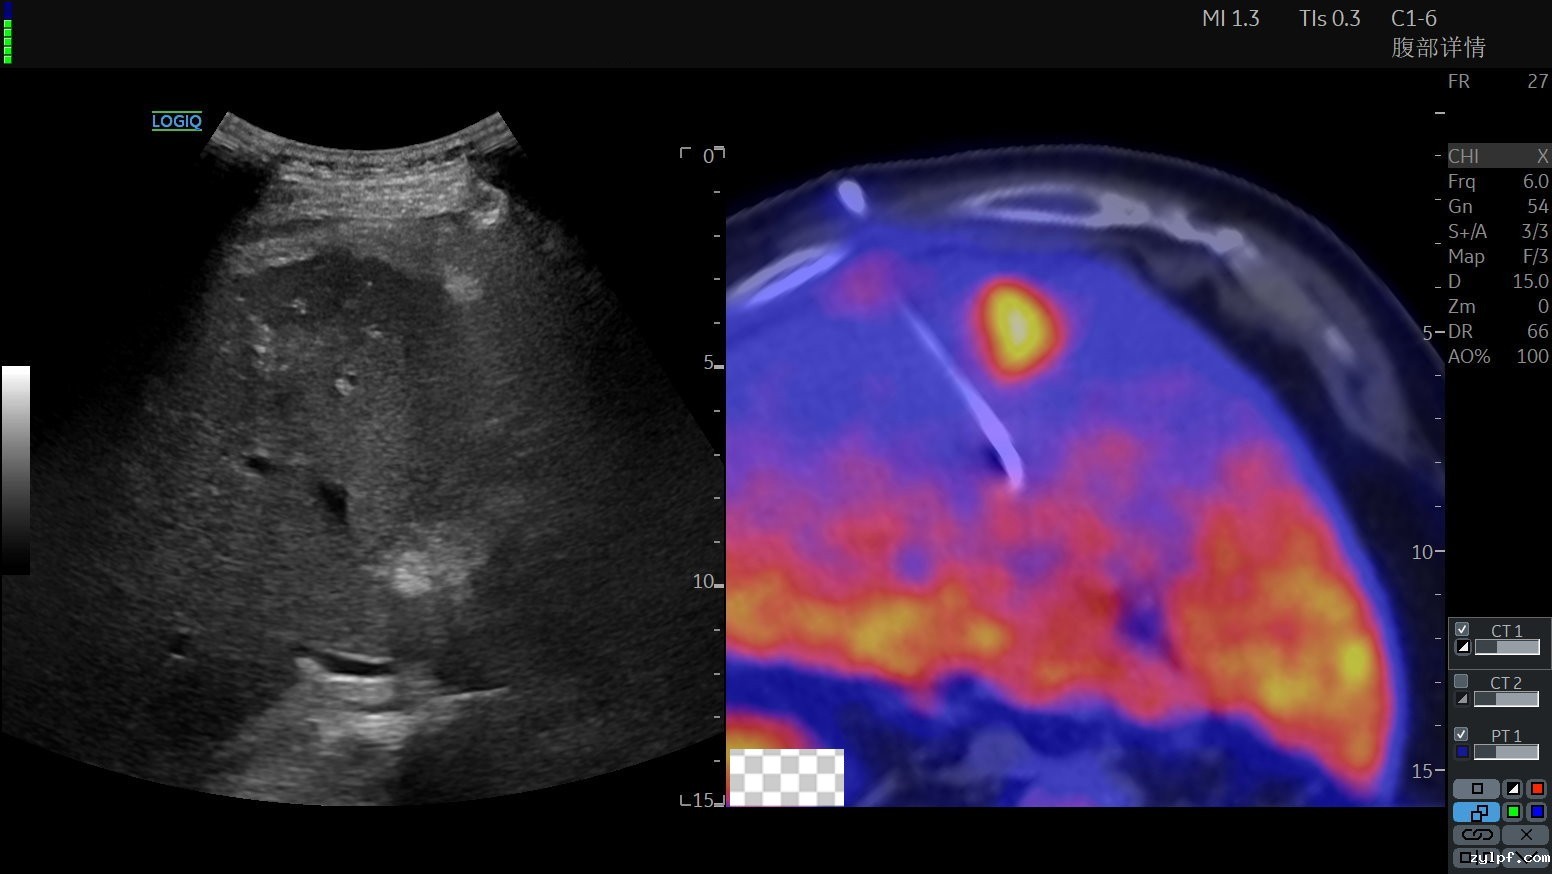

超声设备显示的超声融合PET-CT图像,可以看到PET-CT精准显示高代谢肿瘤病变,配准融合后发挥超声影像的实时便捷性,再结合PET-CT影像清晰显示的高代谢靶目标

肿瘤医院超声介入科施行超声融合PET-CT引导下穿刺活检,整个过程仅需10-15分钟,既精准,又安全有效率。